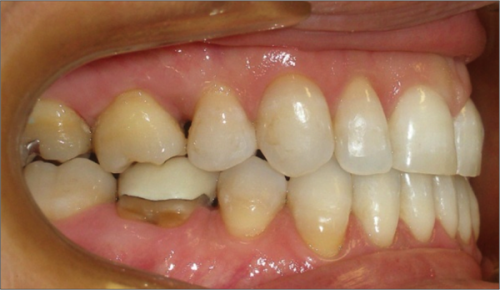

45 year old female:

Diagnosis:

- Missing upper left second bicuspid

- Lower arch crowding

- Edge to edge bite

Treatment:

- Extraction of upper & lower right second bicuspids

- Full fixed appliances

- 21 months